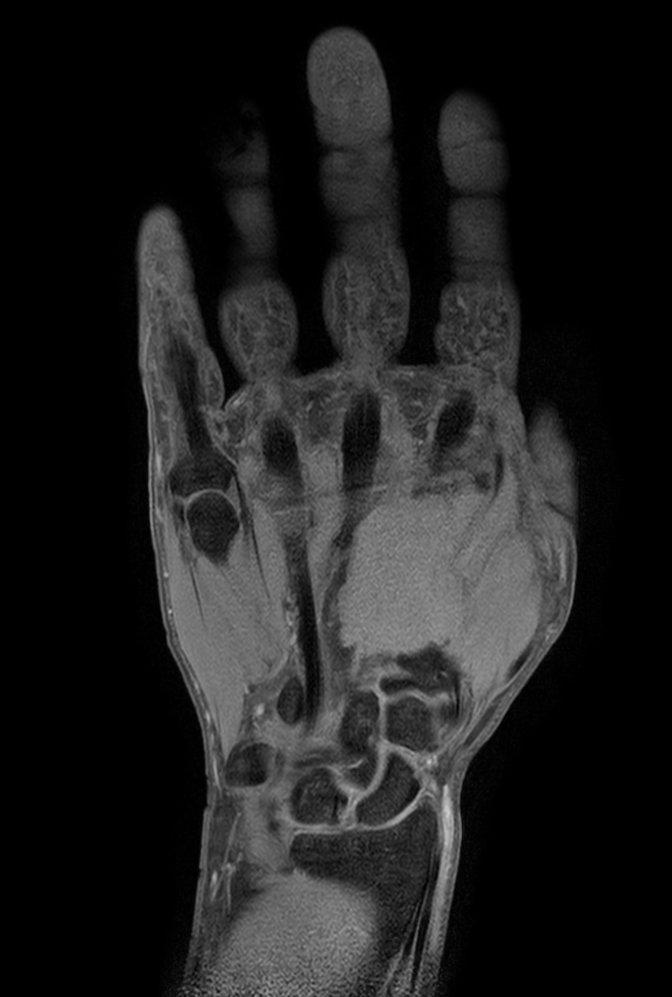

Coronal T1w TSE mDIXON XD (Water only)